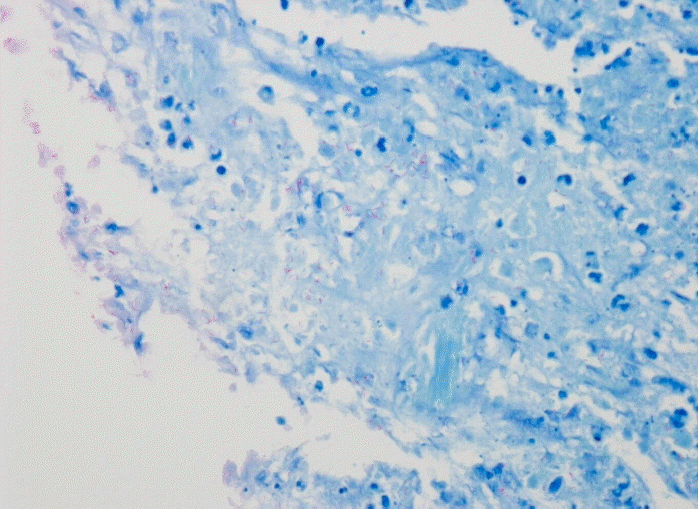

44세 남자가 2008년 10월 보건소에서 시행한 검사상, HIV 항체 양성 소견 보여 본원 감염내과 외래 치료 중으로, 내원 2주 전부터 미열 지속되고 간헐적인 설사와 전신 쇠약감 등을 호소하여 입원하였다. 환자는 10여 년 전 동성애 경험이 있고, 3년 전부터 3차례의 대상포진, 1년 전 칸디다 식도염의 과거력이 있으며, 내원 당시 시행한 검사에서 백혈구 2,600/mm3, CD4 양성 세포 개수 15/mm3, HIV RNA 206,172 copies/μL로, 이에 zidovudine, lamivudine, lopinavir/ritonavir로 고활성 항바이러스 요법(HAART)을 시작하여 유지 중이었다.내원 당시 생체징후는 혈압 110/80 mmHg, 맥박수 80회/분, 호흡수 20회/분, 체온 38.0℃였고, 신체 검진에서 의식은 명료하였고, 만성 병색 소견에, 창백한 결막 소견을 보였다. 목에 촉진되는 종괴 소견은 없었다. 흉부 청진상 호흡음은 깨끗하였고, 심잡음은 들리지 않았으며, 복부 검진상 정상장음이었으며, 촉지되는 종괴나 간 비대, 비장 비대 등의 소견은 없었다. 일반 혈액검사에서 백혈구 2,600/mm3 (호중구 46.0%, 림프구 38.0%), 헤모글로빈 7.6 g/dL, 혈색소 22.0%, 혈소판 187,000/mm3으로 범혈구 감소증 소견을 보였고, 혈청철은 129 ug/dL, ferritin 882.6 ng/dL, UIBC 77 ug/dL, transferrin saturation 62.6%였다. 생화학검사에서 AST/ALT 14/10 IU/L, 총 빌리루빈 0.5 mg/dL, 혈액요소질소/크레아티닌 7/0.9 mg/dL, 총 단백 6.3 g/dL, 알부민 3.1 g/dL, ALP 197 mg/dL이었다. 말초혈액 도말 소견상 정구성 정색소성 빈혈, 백혈구 감소증, 호중구 감소증으로 만성 질환에 의한 빈혈 소견을 보였다. 흉부 방사선 및 복부 단순촬영상 특이소견은 없었다. 환자 내원 당시 시행한 복부 전산화단층촬영상 소장의 장간혈관 주변으로 2개의 괴사된 림프절이 관찰되었으며, 내원 2일째 초음파를 이용하여 복강내 림프절 세침흡인 조직검사를 시행하였다(그림 1). 조직 검사상, Ziehl Neelsen 염색에서 다수의 acid fast bacilli가 만성육아종성 염증소견과 함께 관찰되어 결핵이 의심되었다(그림 2, 3).그러나 함께 시행한 결핵균 중합 효소 연쇄반응에서 마이코박테리아를 나타내는 rpoB gene은 검출되었으나 결핵균에 특이적인 IS6110 gene은 음성으로 비정형 마이코박테리아가 의심되었으며, 조직 배양 검사와 Mycobacteria other than tubercle(MOTT) identification test를 시행하였다(그림 4). 조직 배양에서 마이코박테리아가 동정되었고, MOTT identification test에서 검출된 rpoB gene DNA를 제한 효소 처리하여 조류형 결핵균으로 확진하였다. 환자는 HAART 중 zidovudine이 약제 유발성 빈혈의 원인으로 생각되어 didanosine으로 변경하였고, clarithomycin 1,000 mg/일, ethambutol 1,200 mg/일, rifabutin 150 mg 이틀에 한 번으로 복용하였다. 현재 외래 추적관찰 중으로 CD4 양성 세포는 15개에서 148개로 증가하였고, HIV RNA titer는 206,172 copies/mL에서 95 copies/mL까지 감소 소견을 보이고, 조류형 결핵균 감염과 관련되었던 전신상태 증상들도 호전된 상태로 외래 추적관찰 중이다.

Figure 3.

Numerous acid-fast bacteria were noted on Ziehl-Neelsen stain in mesenteric lymph node biopsy (×1,000).